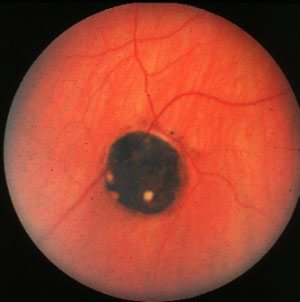

Congenital Hypertrophy of Retinal Pigment Epithelium (CHRPE)

There is a round, well-circumscribed

pigmented lesion. There are depigmented halos within the lesion. Rarely,

there are multiple pigmented lesions in the same area (bear-track

lesions).